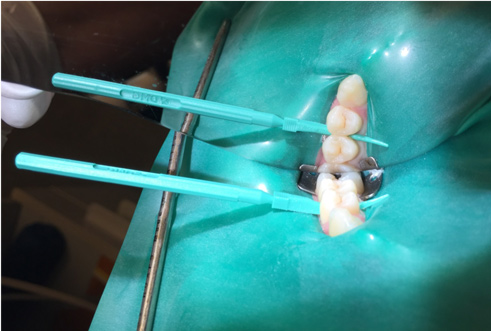

Fig 5. The proximal applicator is inserted with an etch.

Figure 5

5. Insert applicator with resin infiltration material with green side and perforations facing the surface to be treated (Figure 5).

6. Twist the syringe to dispense the 15% hydrochloric acid gel into the proximal contact space. Etch for 2 minutes.